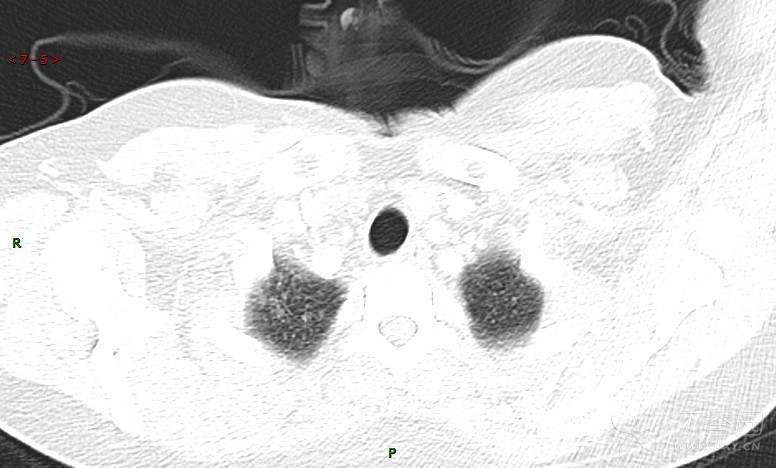

肺内弥漫性网状结节影,PET-CT却无阳性病灶,这是?(附其他2例链接)

女性,58岁,阵发性咳嗽2月,加重1月。

患者于2月前无明显诱因出现咳嗽,以阵发性干咳为主,接触冷空气后咳嗽明显,偶咳少量白色泡沫样痰,咳嗽剧烈时感憋喘,无发热、盗汗,无头痛、头晕,无胸痛、咯血,无恶心、呕吐,无腹痛、腹泻,无尿频、尿痛等不适,于当地医院给予肌注及静脉药物治疗,具体药物名称不详,效果欠佳,近1月来患者咳嗽频率较前增加,咳嗽剧烈时感双侧季肋区疼痛不适,10余天前出现发热,体温在38℃左右,伴畏寒、寒战,无头痛、头晕,无纳差、乏力等不适,药物治疗后体温降至正常,仍阵发性咳嗽,今为求进一步诊治,就诊于我院急诊,因呼吸内科暂无床位,急诊门诊以“肺间质病变”收入急诊留观室,给予“抗感染、止咳”等对症支持治疗后,今日以“肺间质性病变”收入我科,患者自本次发病以来,神志清,精神可,饮食尚可,睡眠一般,大小便正常,体重较前无明显变化。